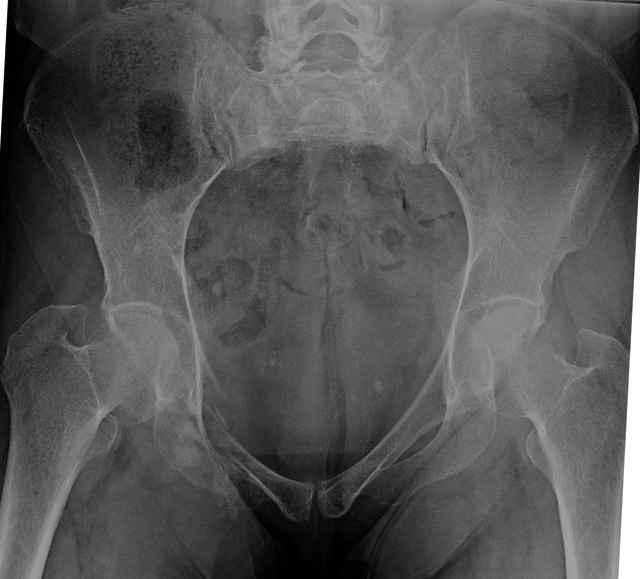

Here are a recent patient’s example slides...

54 yo Female Fell c/o Pain

Initial Films

?Instability on Exam - Limited by Pain

NonOp Initial Mgmt

3 Months After Fall

Continued Pain & Immobility

(+) Instability to Compressive Manual Exam

Pelvic CT Scan - 3 Months After Fall

Sacral Injuries

Ramus Fractures